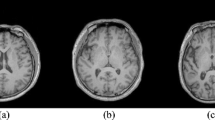

We propose a new method for hearing loss classification from magnetic resonance image (MRI), which can automatically detect tissue-specific features in a given MRI. Sensorineural hearing loss (SHNL) is highly prevalent in our society. Early diagnosis and intervention have a profound impact on patient outcomes. A solution to provide early diagnosis is the use of automated diagnostic systems. In this study, we propose a novel Deep-HLNet framework, based on few-shot learning, for the automated classification of SNHL. This research involves magnetic resonance (MRI) images from 60 participants of three balanced categories: left-sided SNHL, right-sided SNHL, and healthy controls. A convolutional neural network was employed for feature extraction from individual categories, while a neural network and a comparison classifier strategy constituted a tri-classifier for SNHL classification. In terms of experiment results and practicability of the algorithm, the classification performance was significantly better than the standard deep learning methods or other conventional methods, with an overall accuracy of 96.62%.